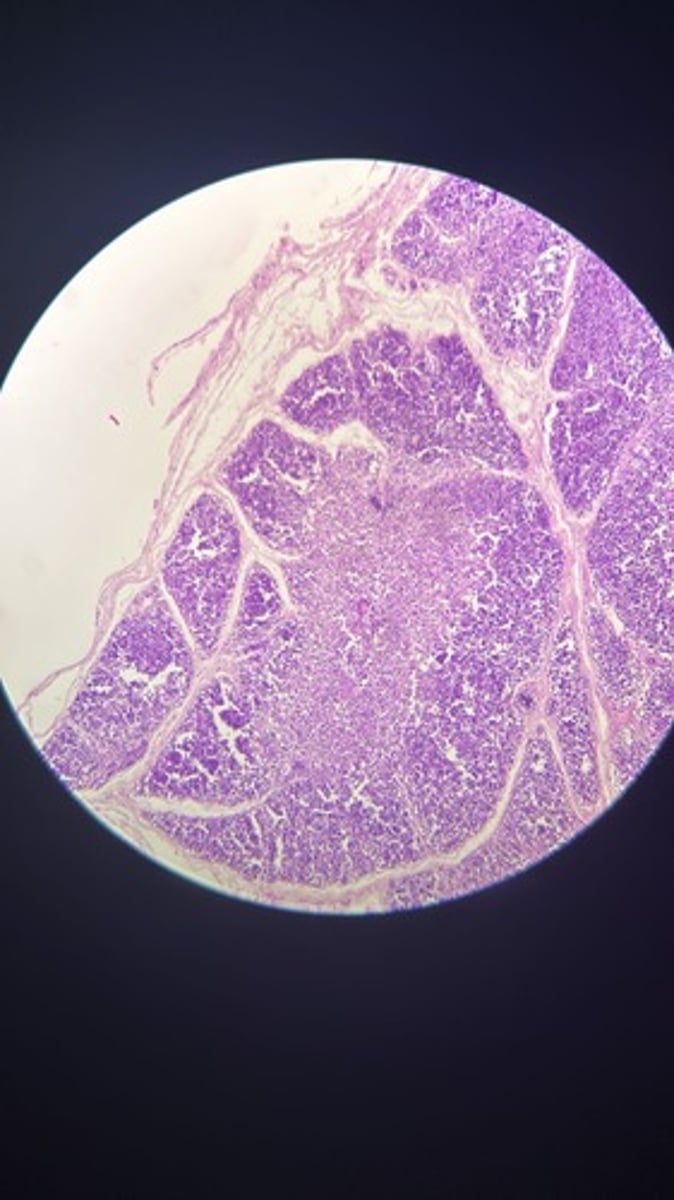

Thymus HE

Thymus HE

Thymus HE

Thymus HE

Thymus HE

Thymus HE

Thymus HE

Thymus HE